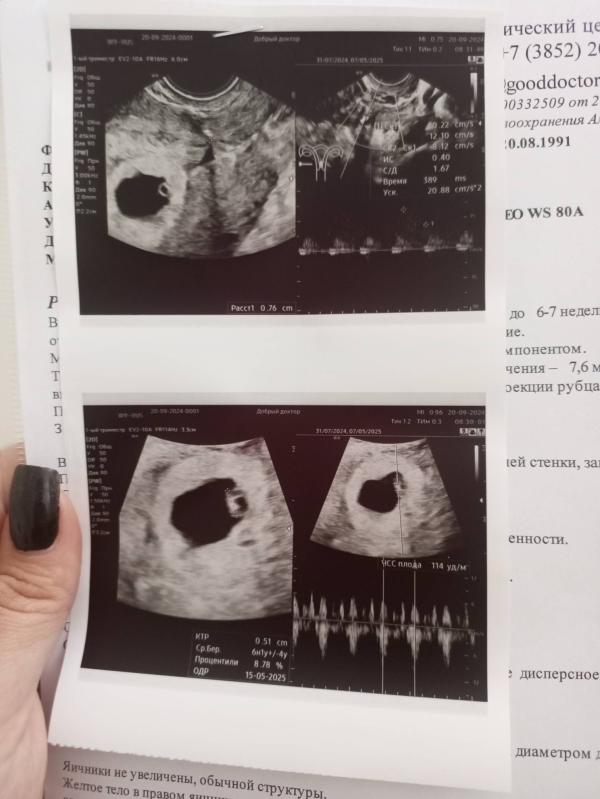

Но главное нашли малыша)))) ктр 5.1 при ПЯ 16мм, чсс 114))))

Растем и развиваемся, срок поставили 6.1, пдр сдвинули пока на 15.05.25)))